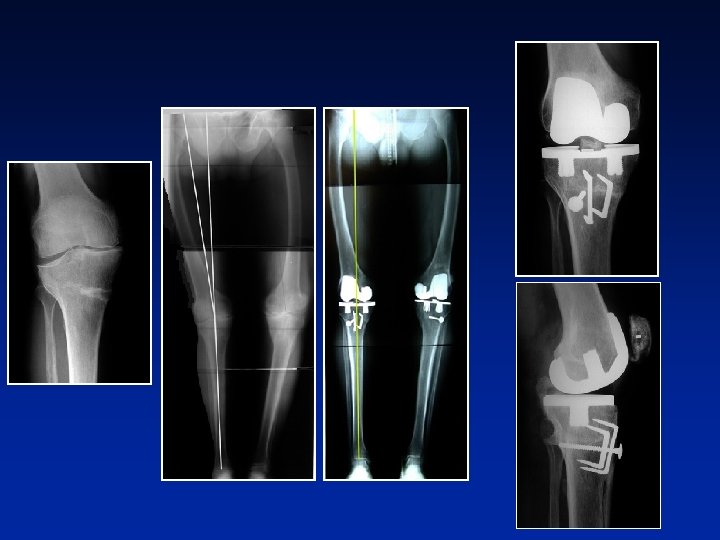

218° Fer… D - 73 anni 13 anni dopo una osteotomia 182°

W. . . D - 60 anni AGC : 191° Appoggio: 2 mesi

138° 180° Fl : 115° Be. . . M - 75 anni Prima osteotomia a 20 anni Trapianto a 4 mesi. Consolidazione a 7 mesi.

166° 180° Prat. . . H - 75 anni 55 anni dopo una osteotomia PTG + osteotomia di apertura

Lu. . 69 anni 153° deviazione maggiore in varo 182° T = 77° PTG con 2 LC

Varo dopo frattura dei 2 piatti tibiali F - 80 anni PTG + apertura con trapianto e 2 cambre

179° F - 71 anni Frattura femorale a 45 anni Prima osteotomia a 61 anni Varo a 2 livelli